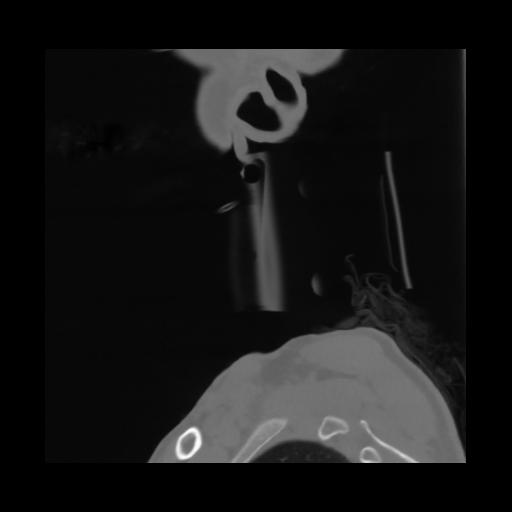

14 P.BLANDAS,,Sagittal,2.000,P.BLANDAS,Sagittal,